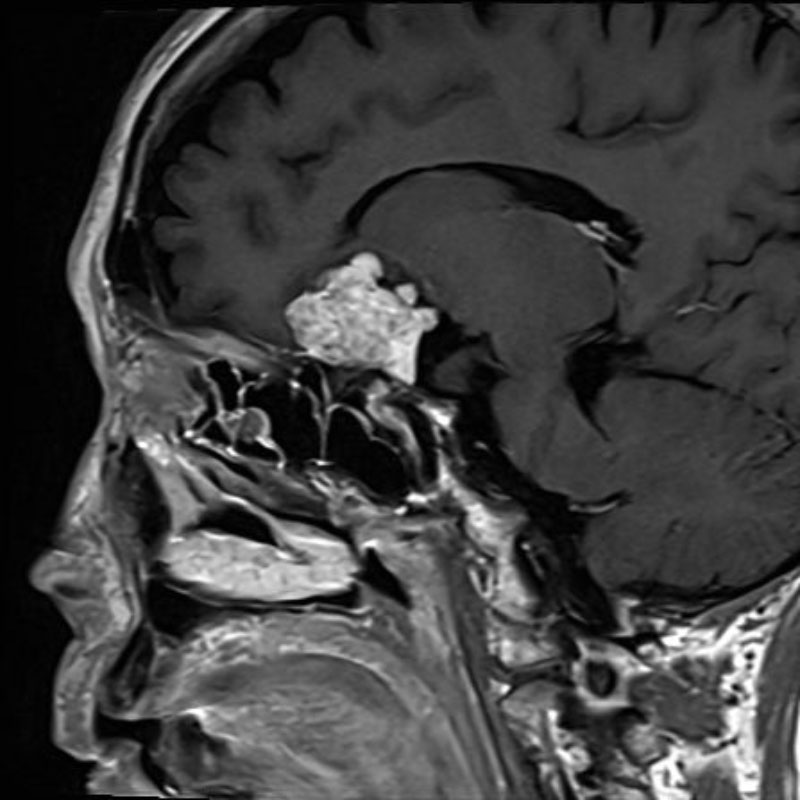

断層撮影

手術前1

手術前2